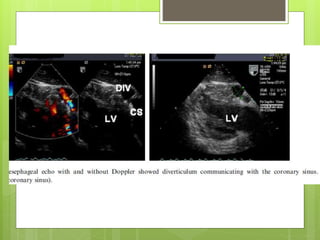

Coronary sinus

diverticulum

 Should be suspected in patient having WPW

syndrome ,refractory to ablation

 Angiography reveals coronary diverticulum

Associated with refractory posteroseptal

pathway